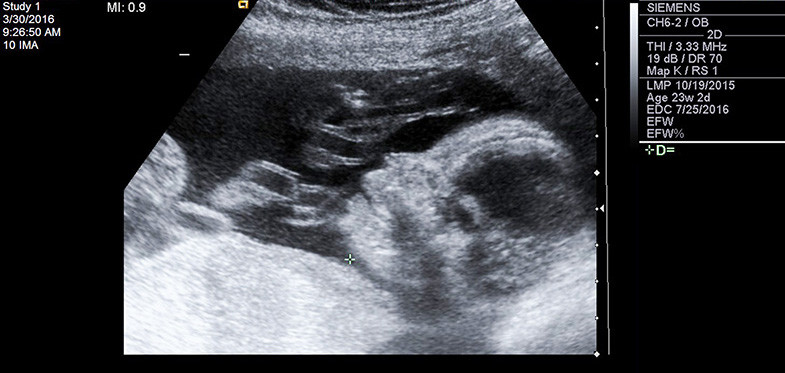

سونوگرافی آنومالی یک جز از غربالگری های مرحله دوم است و در اواسط بارداری انجام می شود و برای مشاهده دقیق تر وضعیت جنین و رحم صورت می گیرد. کارشناس در حین سونوگرافی، مراحل رشد نرمال جنین و محل قرارگیری جفت را بررسی می کند.

- آنومالی اسکن یا سونوگرافی تفصیلی، بین هفته های 18 تا 22 بارداری انجام میشود ولی بهترین زمان برای انجام آن هفته 20 بارداری است. در هفته بیستم بارداری صورت و دست های جنین قابل مشاهده است. مشاهده جنین در سونوگرافی هیجان انگیز است و می توانید همسر یا یکی از اعضای خانواده را همراه با خود ببرید و لحظات شاد و زیبای خود را با آنان تقسیم کنید.

کارشناس ضربان قلب جنین و قسمت های مختلف بدن او از جمله صورت و دست ها را بررسی می کند. با اینکه مشاهده اندام جنین برای شما دشوار است اما کارشناس سطح مقطع آن ها را بررسی می کند. استخوان های جنین در سونوگرافی سفید دیده می شوند و اندام های نرم به رنگ خاکستری دیده می شوند آب دور جنین نیز به رنگ سیاه دیده می شود.